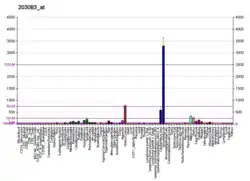

- Adolph KW (May 1999). "Relative abundance of thrombospondin 2 and thrombospondin 3 mRNAs in human tissues". Biochemical and Biophysical Research Communications. 258 (3): 792–6. doi:10.1006/bbrc.1999.0710. PMID 10329465.